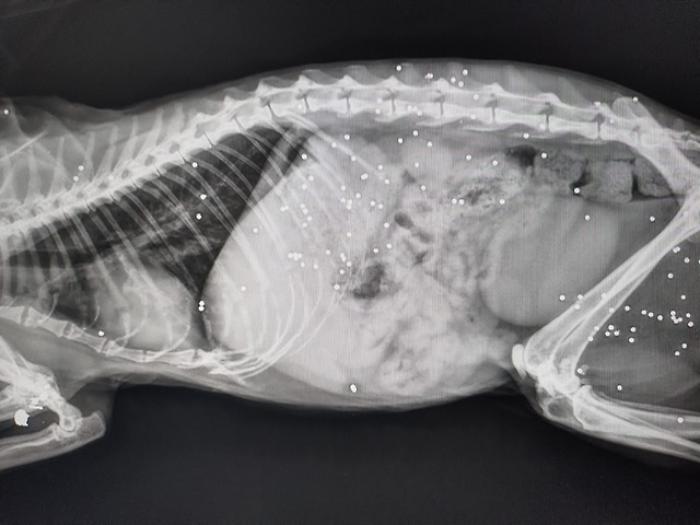

I pallini che hanno raggiunto il felino

La situazione dell’altra gatta - fanno sapere - è ancora più critica: oltre alla zampa seriamente danneggiata, presenta numerosi pallini di piombo nel corpo. I veterinari stanno valutando con grande attenzione come intervenire per salvarle la vita.